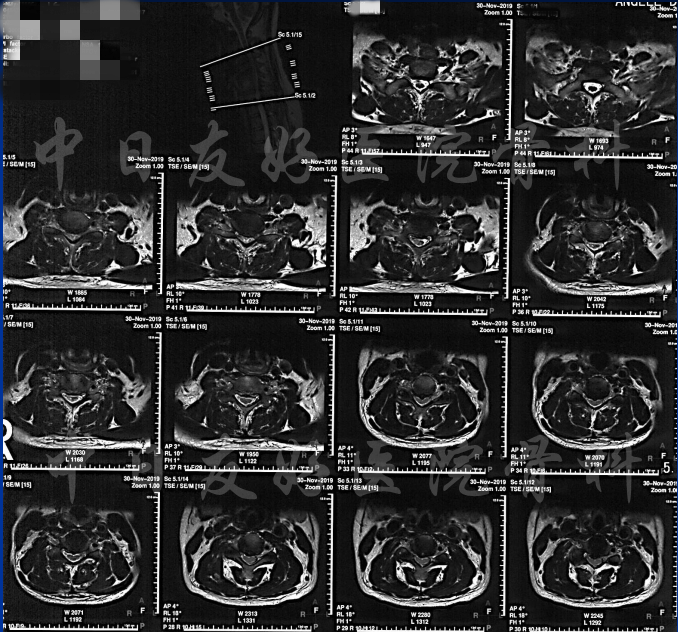

颈椎各节段MRI(上下滑动)

颈CT(上下滑动)

腰椎MRI